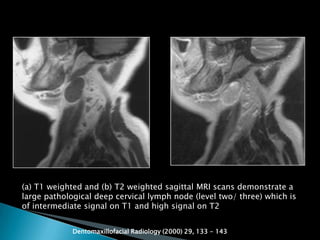

 T1-weighted images depict lymph nodes as

being of intermediate signal intensity,

similar to muscle, whilst T2-weighted

images show them as hyperintense signal.

(a) T1 weighted and (b) T2 weighted sagittal MRI scans demonstrate a

large pathological deep cervical lymph node (level two/ three) which is

of intermediate signal on T1 and high signal on T2

Dentomaxillofacial Radiology (2000) 29, 133 - 143